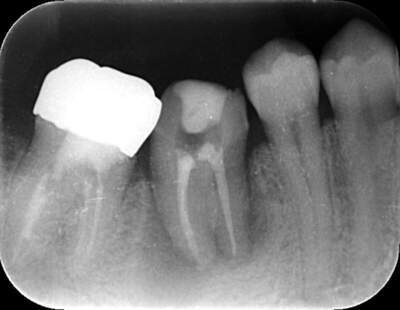

2021.4.3 定期検診時

この時はまだ症状がなかった

しかし歯は縦に割れており、いつ痛みが出てもおかしくないような状態であることは説明していた。

2022.1.15 根尖性歯周炎の急性化

疼痛ありで急患来院。

前々から爆弾抱えているような物で、何かあったら抜歯と伝えていた部位。以前よりクラウンマージン下で歯根縦破折であったが、症状なしで経過観察をおこなっていた。

抜歯予定とし、アモキシシリンとロキソニンを処方した。

レントゲン写真

根管治療後3ヶ月です。根のまわりの骨がやや白くなってきているのがわかります。だんだん骨の添加がみられている証拠になります。

ここまで治癒していればかぶせ物をかぶせても問題ないと判断しました。

最後のレントゲンでは、骨がしっかり添加され、周囲組織となんら変色ない状態にまでなっていることがわかる。